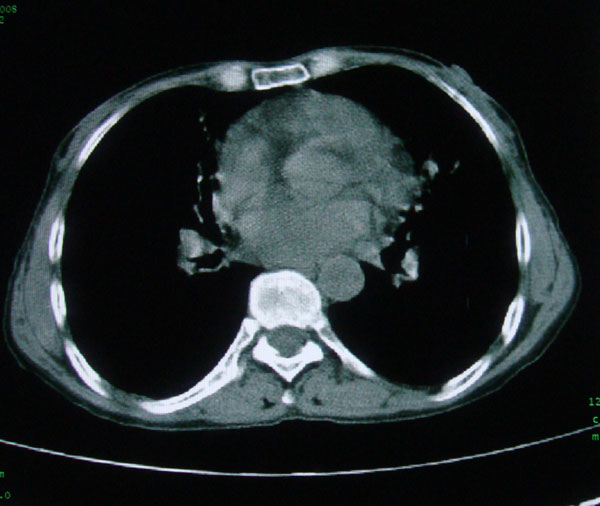

标题: CT15046:F59Y,咳嗽间断咳血丝痰就诊. [打印本页]

标题: CT15046:F59Y,咳嗽间断咳血丝痰就诊.

咳嗽\间断咳血丝痰就诊.

考虑支气管扩张并感染

慢性支气管炎伴支气管扩张\\感染

肺间质性改变 支气管扩张合并感染

慢性支气管炎伴全小型肺气肿、支气管扩张、感染、间质纤维化。